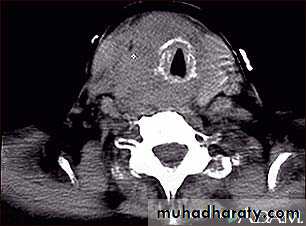

3-CT scan and MRI: assessment of known malignancy, extent of retrosternal and occasionally recurrent

Goitres.